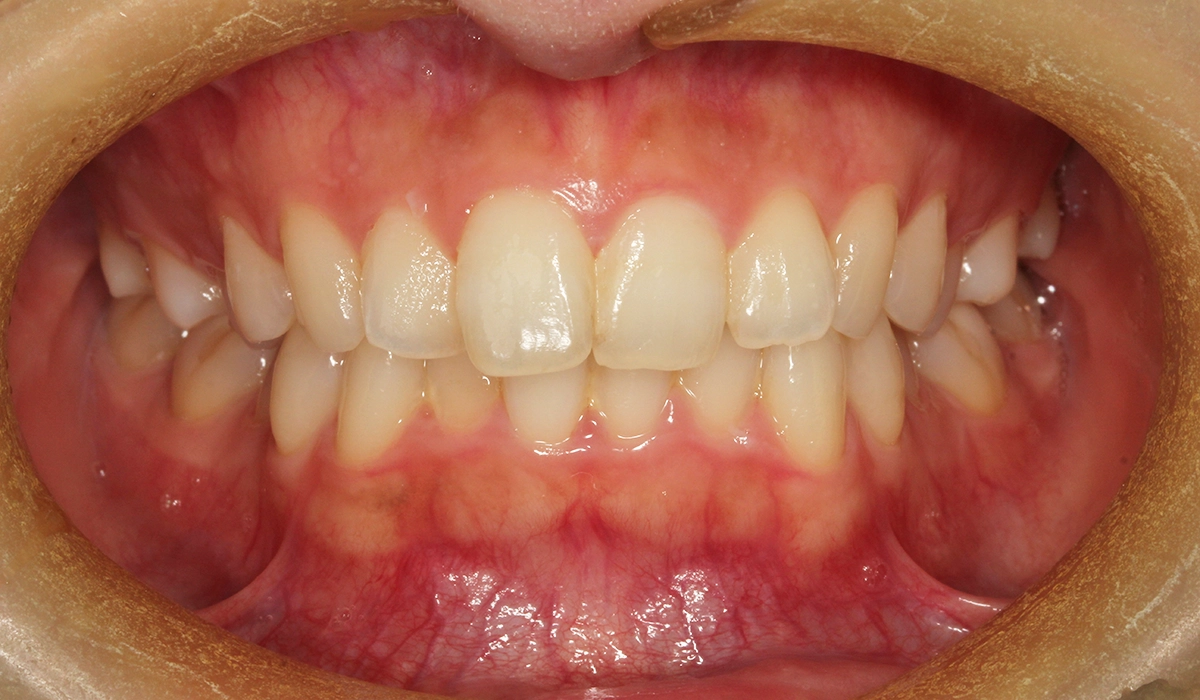

術前:正面

今回ご紹介する患者様は、全体的な歯列のがたつきを気にされており、検査後Ⅰ級叢生と診断。

非抜歯と可能な限りIPRなしにこだわったため、大臼歯の遠心移動を主体としてスペースを確保したため治療期間がやや長くなるも18カ月で完了致しました。